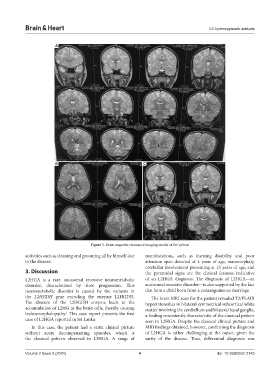

Figure 3. Brain magnetic resonance imaging results of the patient

the L2HGDH gene encoding the enzyme L2HGDH. The brain MRI scan for the patient revealed T2/FLAIR

The absence of the L2HGDH enzyme leads to the hyperintensities in bilateral symmetrical subcortical white

accumulation of L2HG in the brain cells, thereby causing matter involving the cerebellum and bilateral basal ganglia,

leukoencephalopathy. This case report presents the first a finding consistently characteristic of the classical pattern

case of L2HGA reported in Sri Lanka. seen in L2HGA. Despite the classical clinical picture and

In this case, the patient had a static clinical picture MRI findings obtained, however, confirming the diagnosis